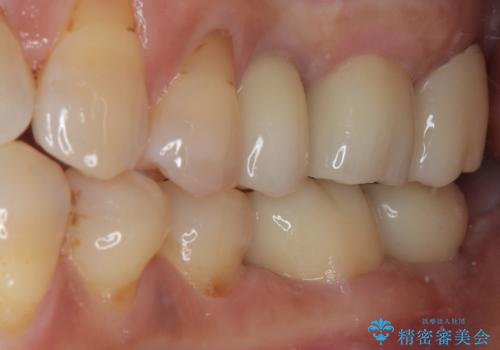

骨よりも深く進行したむし歯 即時荷重インプラントでの短期間治療

- 左下奥のクラウンに違和感を感じるとのことで来院された患者様です。

最後方歯は歯槽骨よりも深い部分にまでむし歯が及んでおり、患者様と相談の上、インプラントによる補綴治療を行うこととしました。

根尖部の病変が小さいことから抜歯即時埋入が選択されるところですが、抜歯窩洞が大きくなることと、窩洞直下に神経や血管が走行していることから、抜歯してから2,3ヶ月待機してから埋入することとしました。

手前の歯は、適合の悪いクラウンを最後方歯と同時にオールセラミッククラウンにて補綴治療を行うこととしました。

骨の高さが不十分であったため、インプラント強度を維持しながらも高さの小さいインプランを使用しました。